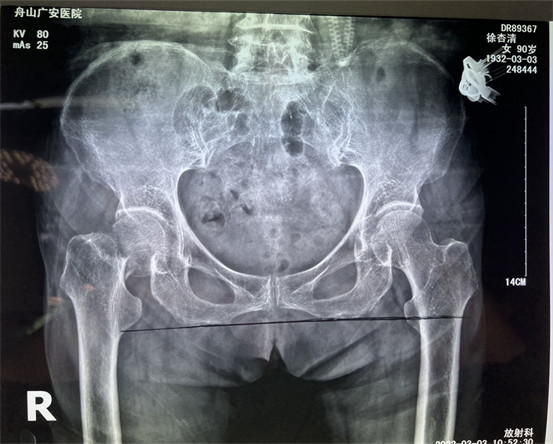

幾周之前,90歲高齡的老太太行走時不慎摔倒,發(fā)生股骨頸骨折,合并心臟病等多種內科疾病。股骨頸骨折的危害極大,常發(fā)生于七十、八十歲嚴重骨質疏松的老年人,如果不能給以合適的手術治療患者會喪失行走能力,同時臥床時間長會才出現許多并發(fā)癥,危及生命。

在舟山廣安醫(yī)院辦理住院后,經過白黎明副主任和骨科中心羅軍主任的系統檢查和全面評估后,決定為患者做了微創(chuàng)智能DAA人工髖關節(jié)置換。